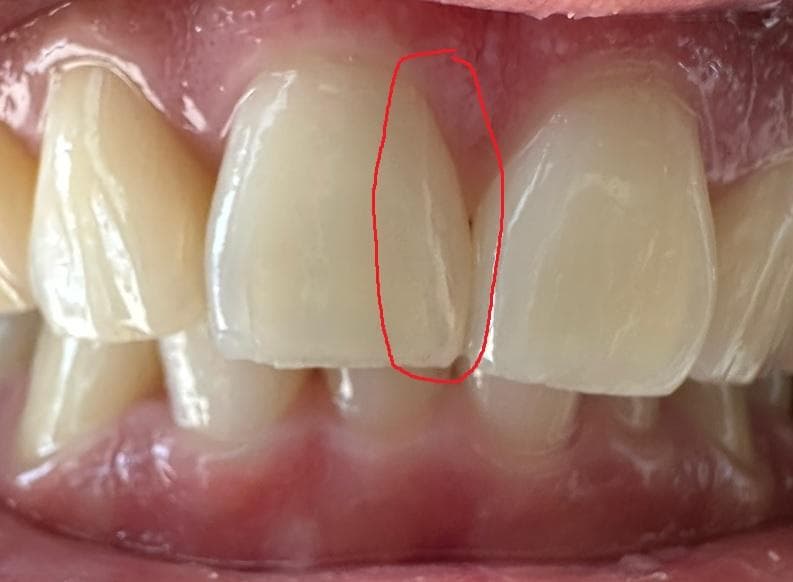

빨간색으로 표시한 선이 크랙인가요? 아니면 그냥 크레이지 라인(실금)인가요?

증상이 없다면 실금입니다. 이런 경우 당장은 치료가 필요하지 않습니다. 하지만 사진을 보니 동일 치아의 끝부분도 조금 깨져나갔네요. 평소 앞니에 힘이 많이 가해지는 것 같으니 가급적 앞니로 베어물거나 뜯어야하는 음식들은 작게 잘라서 드시고, 질기거나 단단한 음식은 피해주시는게 좋을 것입니다. 금이 간 부분은 시간이 지나도 회복되지 않고 점점 진행만 되기 때문에, 힘을 잘못받으면 금이 치아안쪽까지 진행될 수 있습니다. 그렇게 되지 않도록 최대한 조심해서 사용하세요.

사진으로만 봤을 경우에는 정확한 확인이 어려워 보입니다. 하지만 크랙의 가능성 커보이지는 않습니다.

명확히 크랙라인이 보이긴 하나 내부까지 진행되지 않아 증상은 없는 것 같습니다. 말씀하신 craze line (실금, 치관잔금)보다는 좀 더 진행된 단계이긴 합니다.